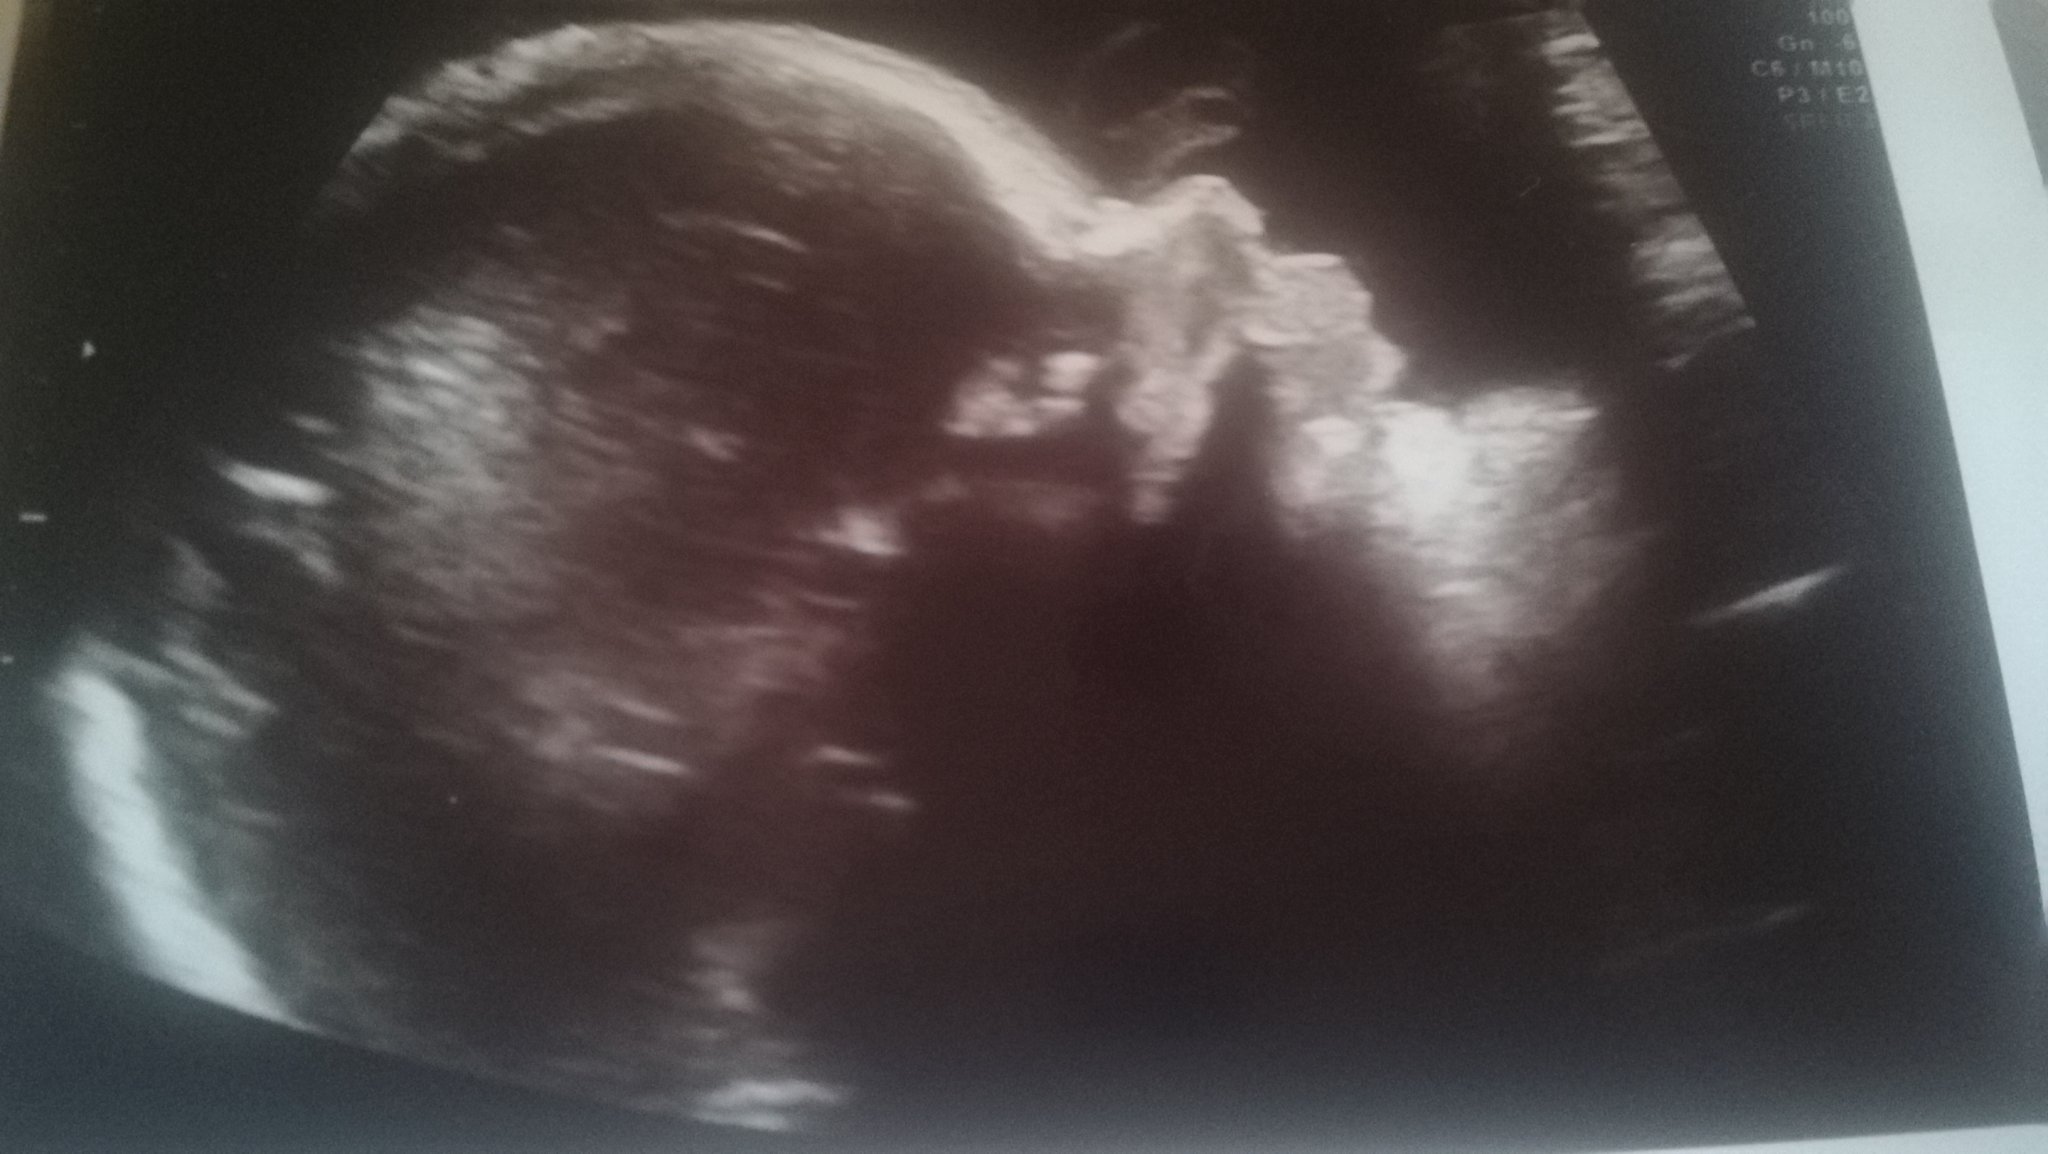

Виждам , че на повечето от вас бебетата вървят с няколко дни по-големи . На консултацията 26+0 измериха бебето 800 гр. и казаха, че го измерват с 4 дни по-малко. Знам, че е относително, но все пак ме налегнаха едни мисли....